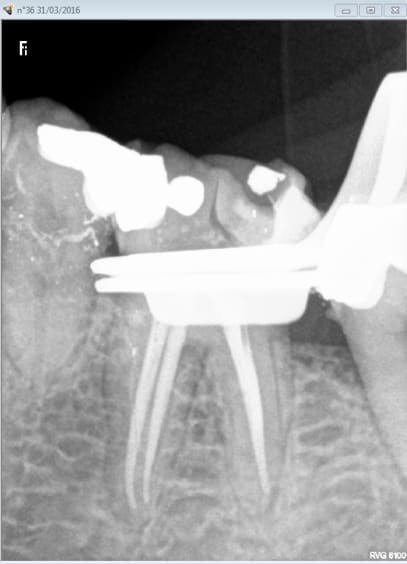

je suis toujours surpris par la force des collages. Meme monté fin la paroi de la reconstitution pré endo tient le choc face au crampon. -)

C'est quand meme curieux cette zone radio claire entre le luxacore et la dent , excès d'agent de liaison ? Parce que espace il n'y a pas.

Capture d e cran 2016 03 31 18.54 - Eugenol

Capture d e cran 2016 03 31 18.59 - Eugenol